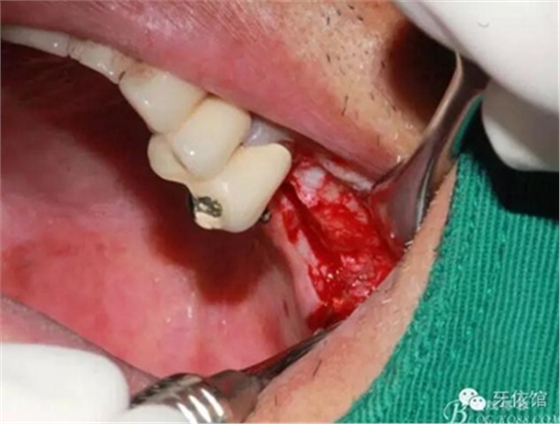

右上5頰側(cè)粘膜竇道,腫脹,膿性分泌物

右上5拔牙窩內(nèi)掻刮出大量肉芽組織

剝離右上6,7頰側(cè)